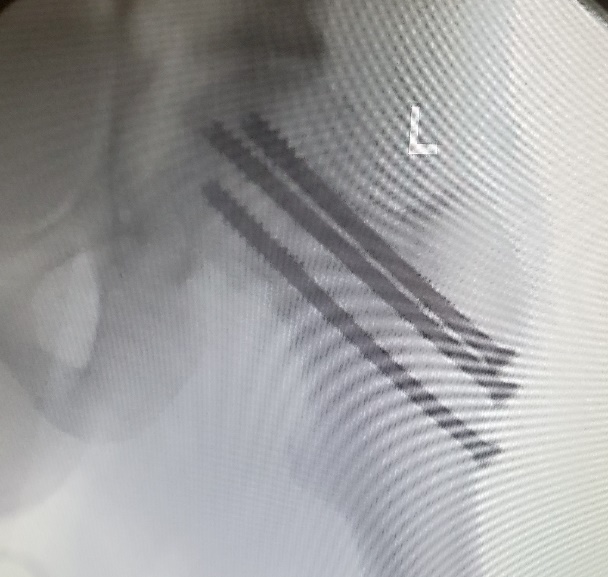

Left femoral neck fracture treated with valgus reduction and parallel screw fixation

Left femoral neck fracture treated with valgus reduction and parallel screw fixation.